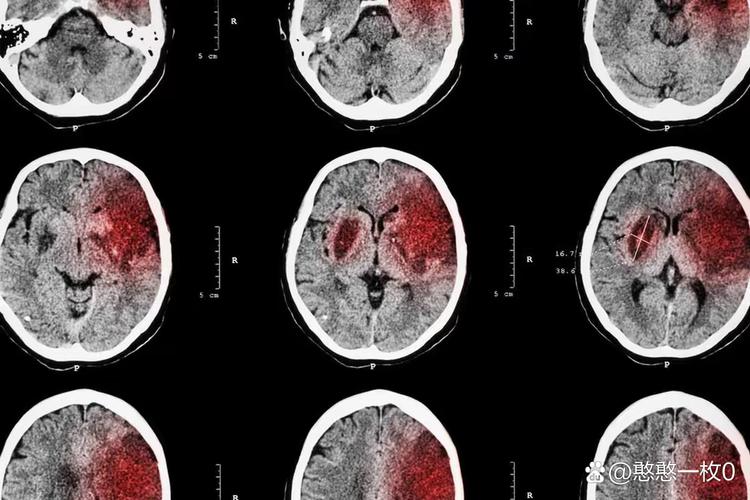

容易引起大面积脑水肿

侧脑室旁区域空间相对较大,一旦发生梗塞,梗塞区域的细胞会迅速死亡,导致血管通透性增加,引发严重的脑水肿,由于侧脑室是大脑内的一个空腔,周围水肿会向压力较低的脑室中心挤压,导致颅内压急剧升高。

颅内压增高是极其危险的,它会:

- 压迫健康的脑组织,导致神经功能进一步恶化。

- 使脑组织移位,可能形成脑疝,这是脑梗最致命的并发症之一,会迅速导致昏迷、呼吸心跳停止,死亡率极高。

虽然侧脑室旁本身不是“生命中枢”(脑干才是),但严重的脑水肿会向上压迫间脑和脑干,影响维持心跳、呼吸和血压的基本生命功能。